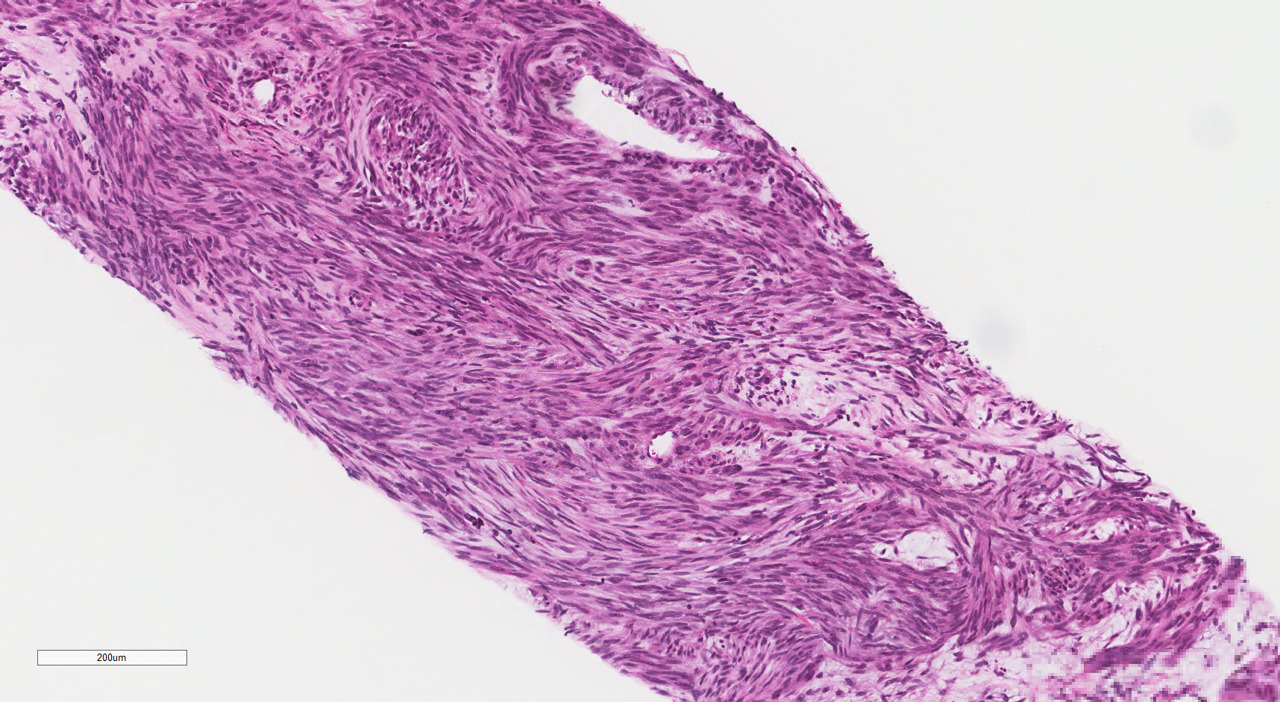

The patient was discharged home on postpartum day seven. At her surgical oncology appointment four weeks later, she continued to show signs of malnutrition with a weight loss of 20 kg compared to her intrapartum weight. An ultrasound-guided biopsy of her retroperitoneal mass confirmed the diagnosis of GIST with spindled morphology and multiple liver metastases (Figures 4 and 5). The patient’s case was reviewed in a multidisciplinary gastrointestinal tumor board, where neoadjuvant imatinib therapy was recommended. At her follow-up visit, the patient reported an increased appetite, and the size of her abdominal wall mass had decreased by approximately half. Due to an excellent initial response to imatinib therapy, this was to be continued with imaging at three-month intervals to assess her disease status; however, this plan was complicated by the SARS-CoV-2 pandemic, as the patient traveled oversees and was unable to return for several months. She did continue to take imatinib without difficulty during this time period.